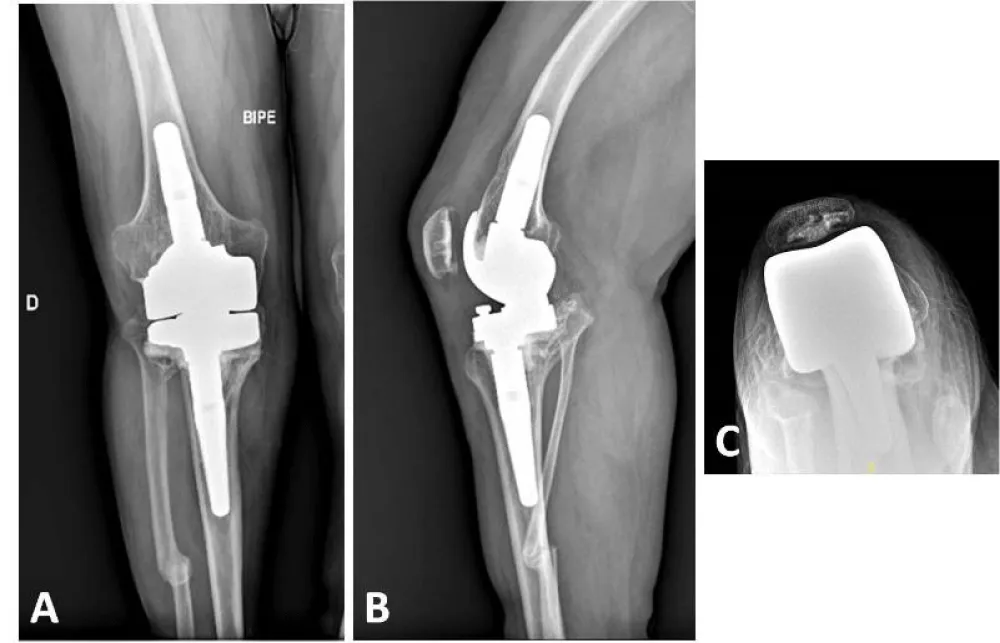

X-rays reveal severe deforming osteoarthritis of the right knee with a medial tibial metaphyseal angle of 53.6° (Figure 1). Telemetry shows medialization of the weight-bearing axis of the right lower extremity due to severe genu varum (Figure 2). Computed tomography (CT) confirms joint destruction with varus deformity of the proximal tibia (Figure 3), and severe misalignment of the posterior tibial slope (Figure 4).

Subsequently, an X-small-sized rotating hinge total knee arthroplasty was implanted. Despite the small bone size, the femoral cage was successfully completed without fracturing or weakening the femoral condyles. Uncemented stems, measuring 14 mm thick and 50 mm long in the femur, and 10 mm thick and 80 mm long in the tibia, were placed. Additionally, a 20 mm distal lateral femoral augment and a 5 mm medial tibia augment were necessary. Bone sections were completed using intramedullary guides (Figure 8).

Twelve months postoperatively, the patient was able to walk without pain or the need for external assistance. The patient’s range of motion was acceptable, with active extension of 0° and flexion of 90°. The radiological evaluation revealed the absence of radiolucent lines or migrations of prosthetic components, along with consolidation of the fracture line distal to the femoral stem (Figure 9). With two years of follow-up, the patient is leading an active life without significant limitations due to his knee surgery, and is highly satisfied with the clinical outcome.